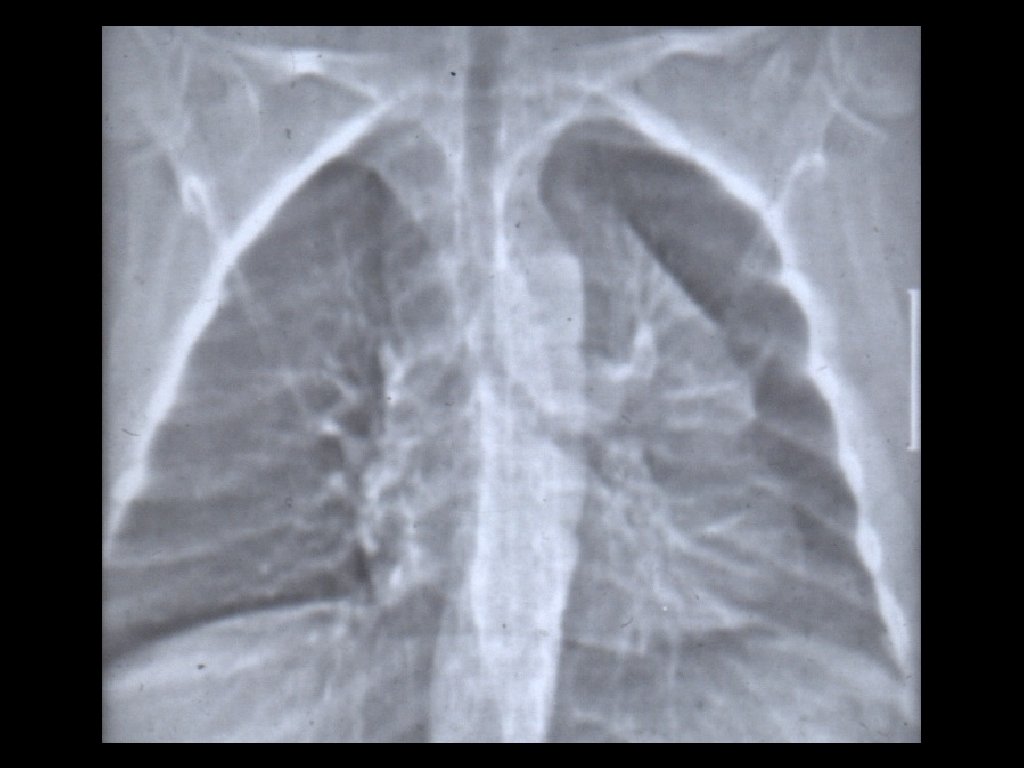

Hipertensiunea arterială pulmonară 1. Hiluri pulmonare cu arie de proiecție crescută, ramificate 2. Decalibrare bruscă a ramurilor de AP în regiunea perihilară; 3. Periferie pulmonară „săracă“ în benzi de desen pulmonar.